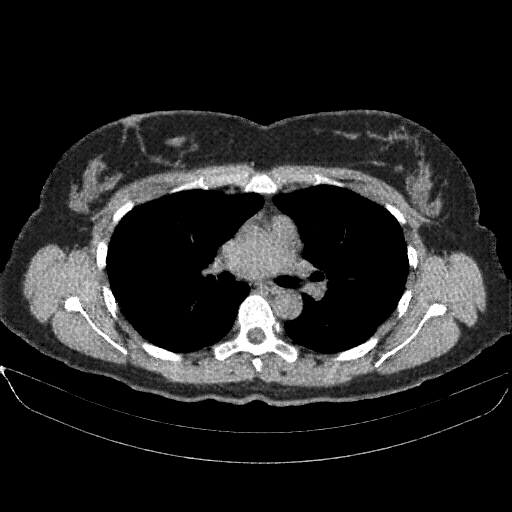

Targeted Slice 70 - Mediastinum Window Analysis (Generated vs Real Venous)

0.741

Mediastinum SSIM

34.8

Mediastinum RMSE

13.6

Mediastinum MAE

Average Mediastinum Window Metrics Across All Slices (170 slices) - Generated vs Real Venous

0.728

Mediastinum SSIM (Avg)

35.8

Mediastinum RMSE (Avg)

14.6

Mediastinum MAE (Avg)

Image Grid

4Γ—3 grid: Rows show different image types (Original NATIVE, Reconstructed NATIVE, Original VENOUS, Generated VENOUS), Columns show windowing techniques (No Window, Lung Window, Mediastinum Window)

Generated VENOUS CT scan (A→B translation)

Full window (WL 1023.5, WW 4095 β†’ Low βˆ’1024, High +3071)